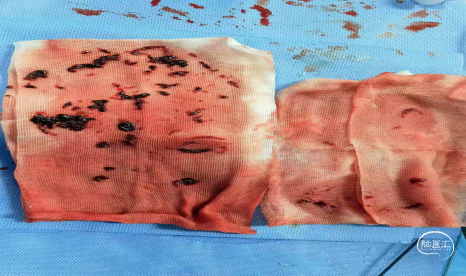

反复抽吸,多次中间管于负压状态下无回血时,负压状态撤出体外,可见大量血栓。